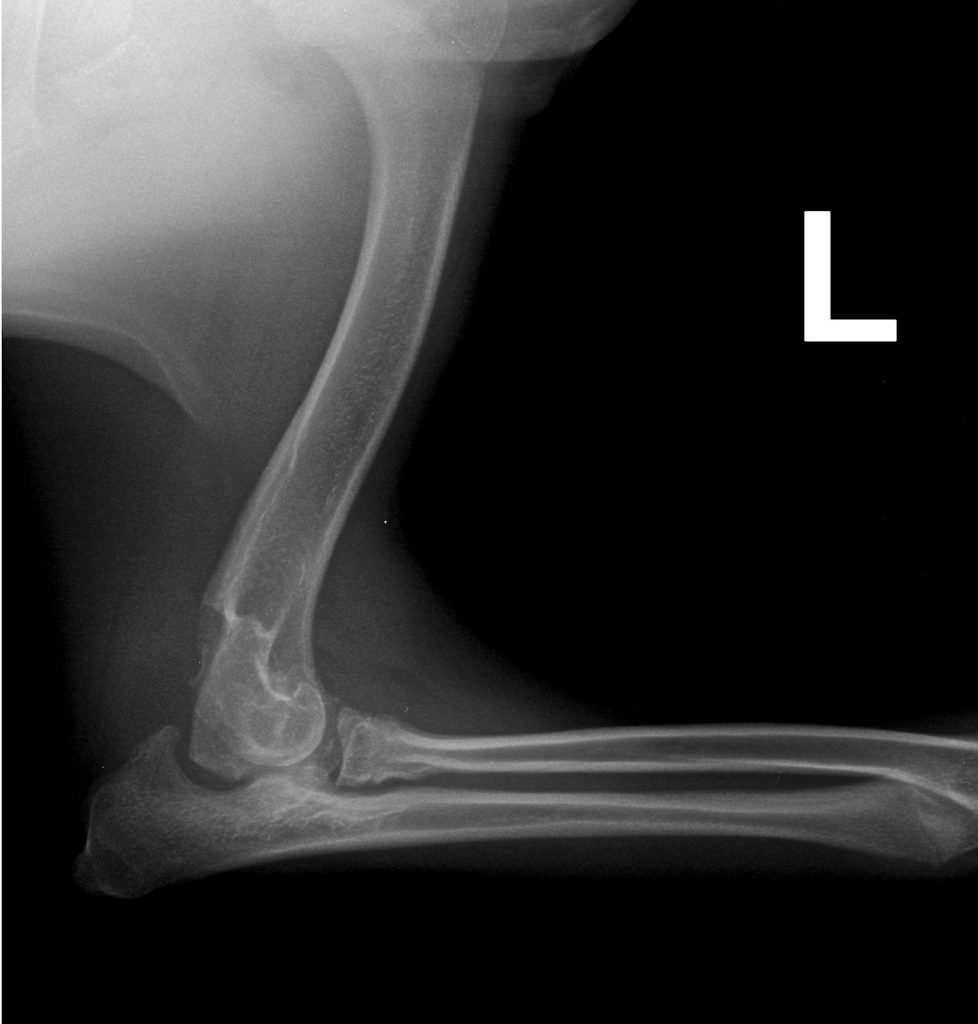

Dysplazje stawu łokciowego

Dysplazje łokciowe u psów to zespół wad rozwojowych stawu łokciowego, które prowadzą do nieprawidłowego obciążenia chrząstki i kości, a w konsekwencji – do rozwoju wczesnej choroby zwyrodnieniowej (artrozy).

Pod pojęciem „dysplazja łokciowa” kryją się cztery główne nieprawidłowości:

- UAP – nieprzyrośnięty wyrostek łokciowy dodatkowy,

- FCP – fragmentacja wyrostka dziobiastego przyśrodkowego,

- OCD – osteochondroza chrząstki bloczka kości ramiennej,

- INC – inkongruencja stawu łokciowego (niedopasowanie powierzchni kości).

Wszystkie te zmiany mogą występować pojedynczo lub łącznie. Choroba rozwija się głównie u psów ras dużych i szybko rosnących (np. owczarki niemieckie, labradory, golden retrievery, rottweilery).

Objawy kliniczne

- kulawizna jednej lub obu kończyn piersiowych (często nasilająca się po wysiłku),

- sztywność i niechęć do ruchu,

- ból przy zginaniu/prostowaniu łokcia,

- charakterystyczne „odstawianie” łokci na zewnątrz.

Diagnostyka

- Wywiad i badanie kliniczne – ocena kulawizny, bolesności i zakresu ruchu,

- RTG (rentgen) – podstawowe badanie, choć ze względu na złożoność stawu łokciowego, nie zawsze pozwala wykryć wszystkie zmiany

- TK (tomografia komputerowa) – bardzo dokładna ocena struktur kostnych, szczególnie przy podejrzeniu FCP

- Artroskopia – metoda inwazyjna, ale umożliwia jednocześnie diagnostykę i leczenie (usunięcie fragmentów chrząstki/kostnych).